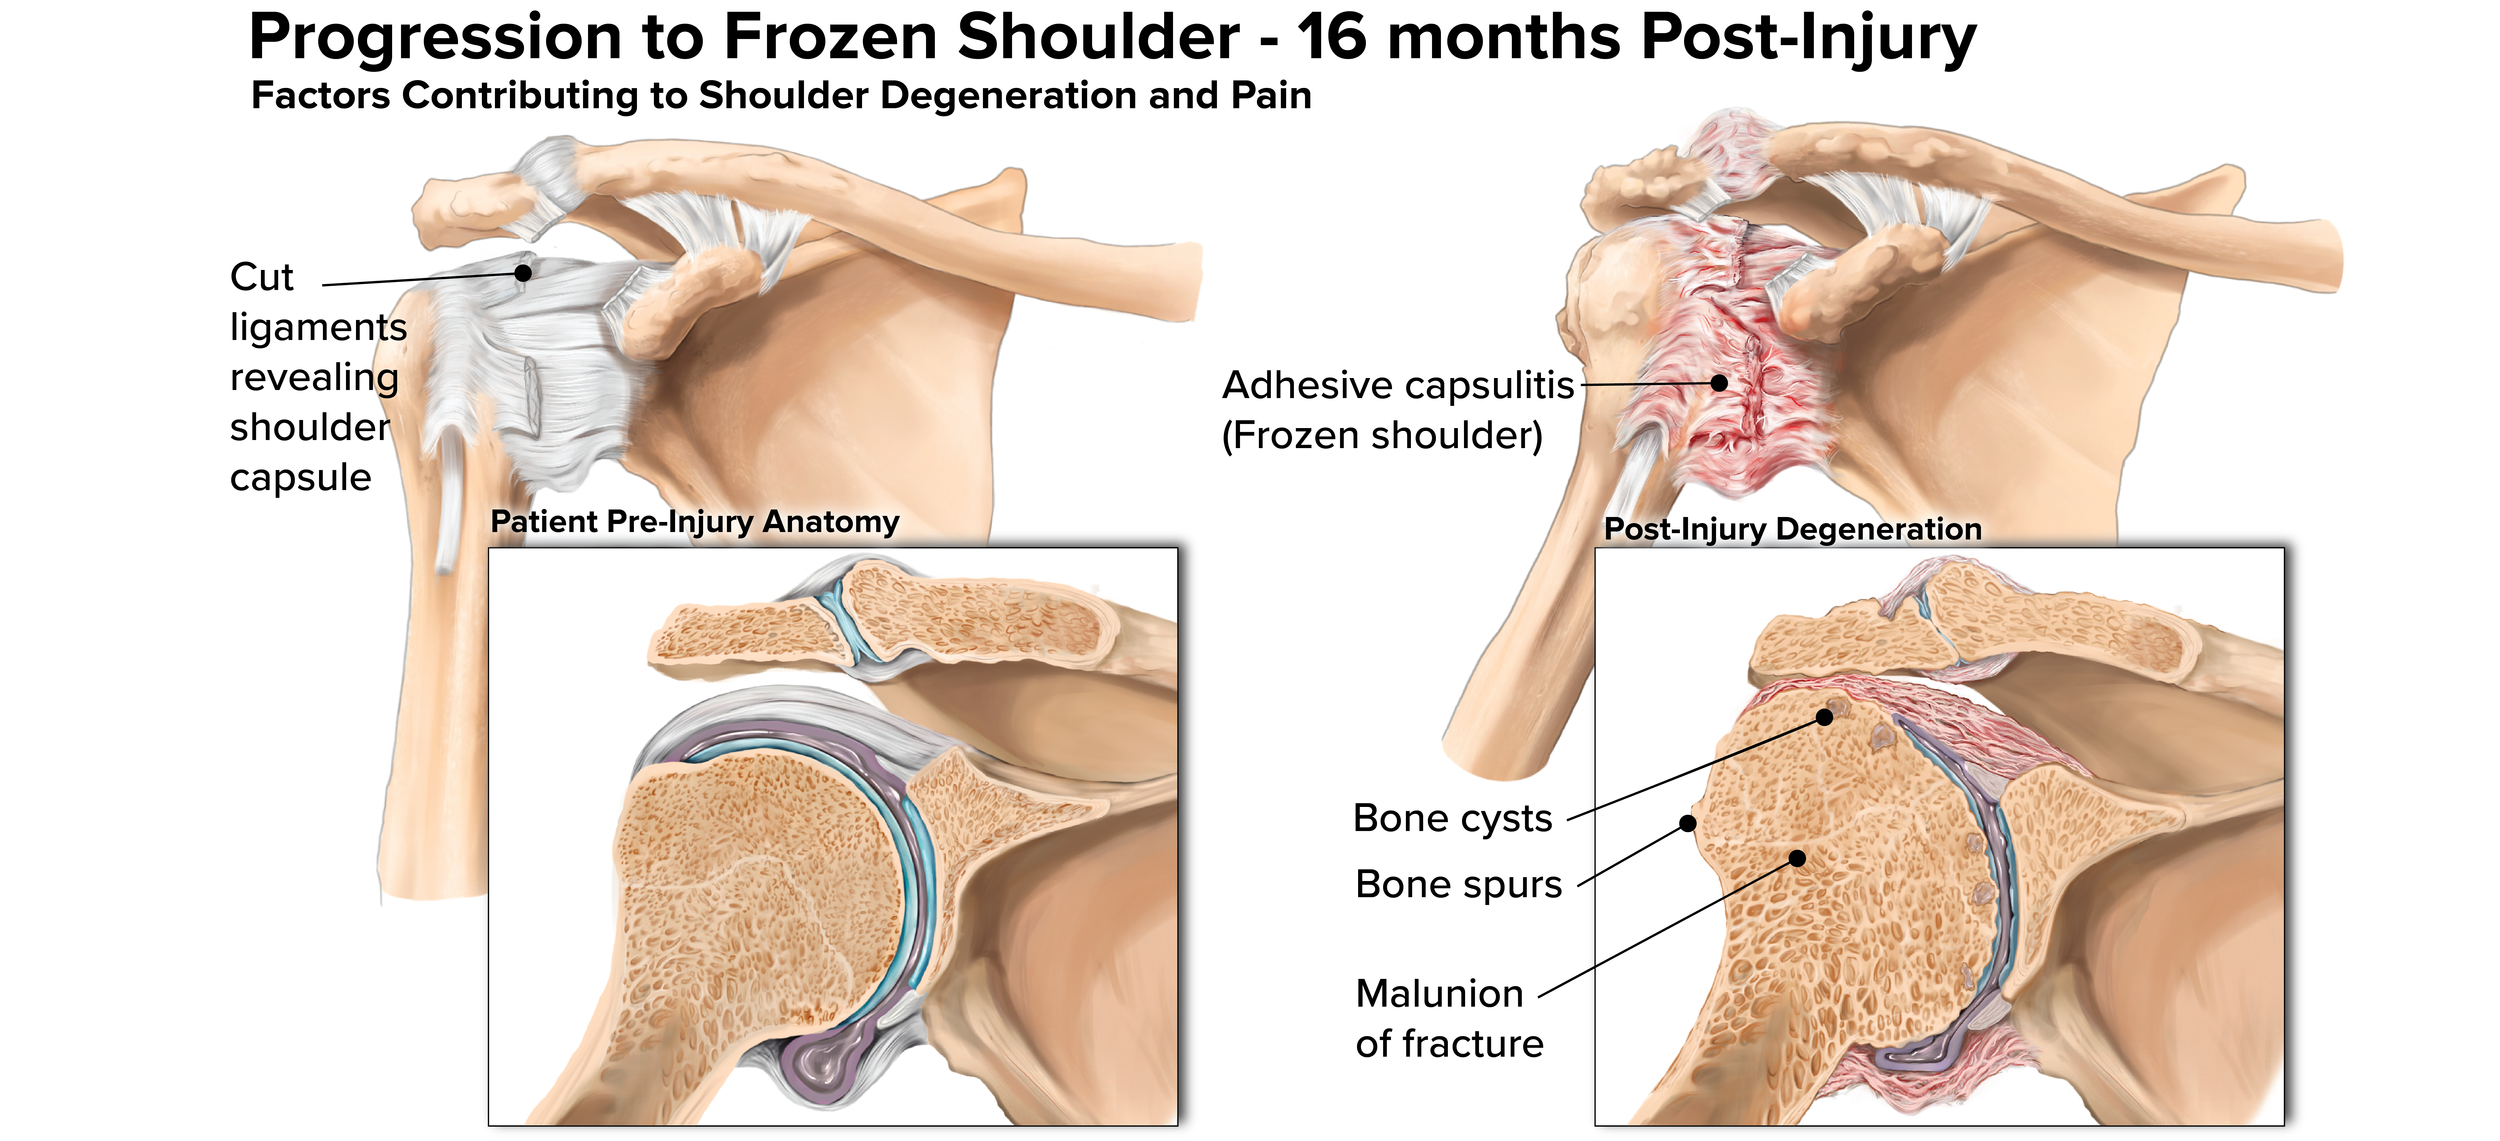

Craniosynostosis Care

Explore a curated collection of our past work, where imagination meets strategy. Each project reflects our drive to deliver thoughtful, effective solutions.

Series: Inclusive Anatomy